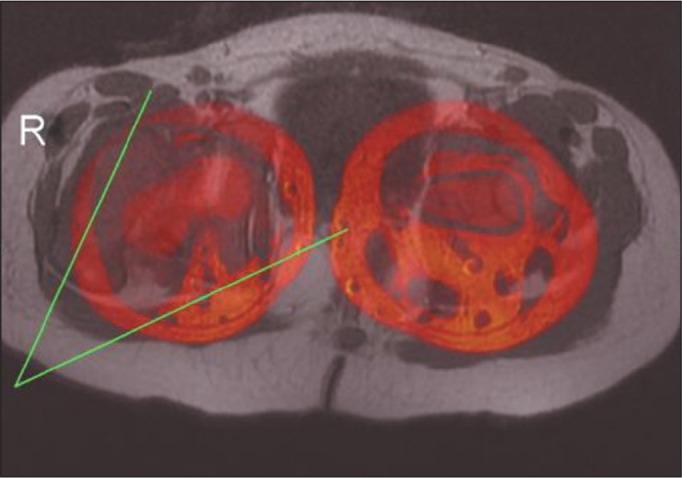

This was a cross-sectional study of 20 consecutive patients with DDH (27 dysplastic hips) who were examined with MRI. In dysplastic and normal hips (DDH and comparison groups, respectively), we evaluated the following parameters: osseous acetabular anteversion (OAA); cartilaginous acetabular anteversion (CAA); femoral anteversion; osseous Mckibbin index (OMI); cartilaginous Mckibbin index (CMI); and the thickness of the anterior and posterior acetabular cartilage.

材料与方法

这是一项对20例连续的DDH患者(27个发育不良髋关节)进行MRI检查的横断面研究。在发育不良髋关节和正常髋关节(分别为DDH组和对照组)中,我们评估了以下参数:骨性髋臼前倾角(OAA);软骨性髋臼前倾角(CAA);股骨前倾角;骨性麦基宾指数(OMI);软骨性麦基宾指数(CMI);以及髋臼前后软骨的厚度。

结果

发育不良髋关节的OAA显著更大。正常髋关节和发育不良髋关节之间的CAA、股骨前倾角、OMI和CMI无显著差异。在DDH组和对照组中,OAA显著低于CAA,OMI显著低于CMI,髋臼后软骨显著厚于前软骨。